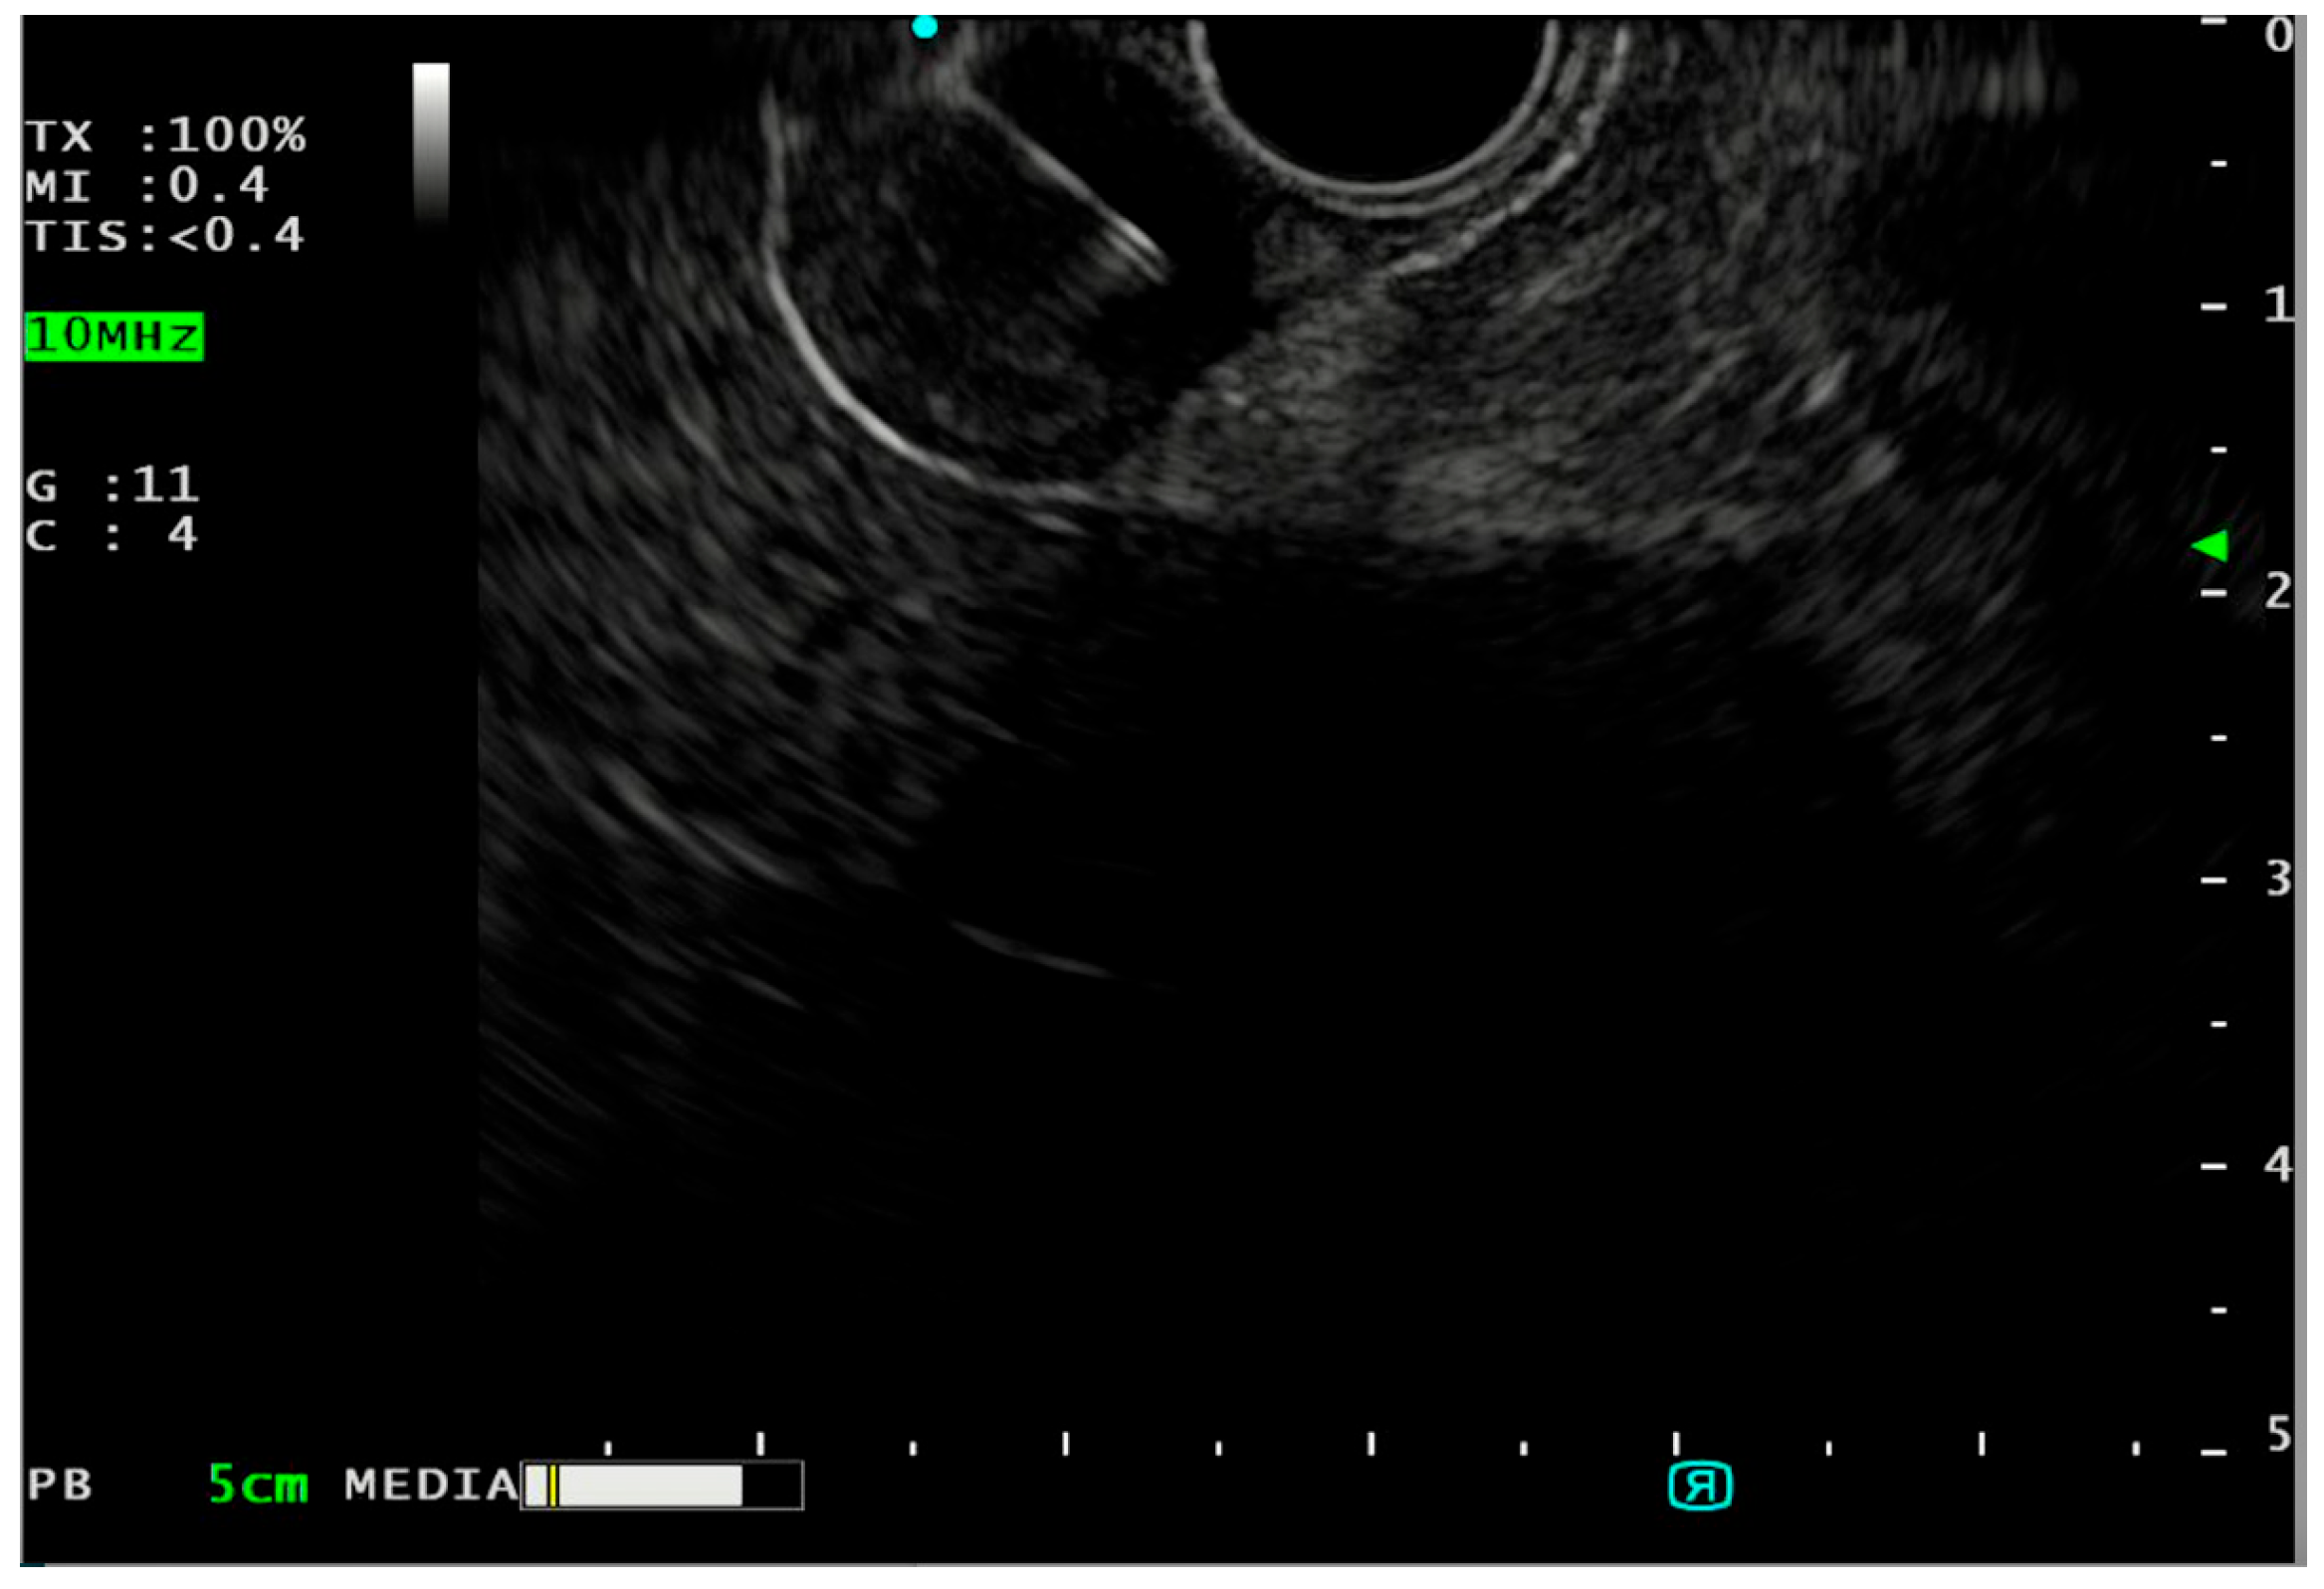

| Subepithelial Lesion | Layer of Origin | Echogenicity | Location in GI Tract | Malignant Potential |

|---|---|---|---|---|

| Lymphoma (5) | 2nd/3rd/4th | Hypoechoic | Anywhere in the GI tract | Yes |

| Lymphangioma (5) | 3rd | Anechoic, no Doppler signal, with internal septa | Small intestine | No |

| Schwannoma (8) | 4th | Hypoechoic, homogenous, sometimes with marginal halo | Stomach (body) | No |

| GIST (9) | 2nd/4th | Hypoechoic, hypervascular, heterogeneous with cystic space or echogenic foci | Stomach | Yes |

| Leiomyoma (11) | 2nd/4th | Hypoechoic, rarely multifocal fine margin | Esophagus | No |

| Varices (11) | 3rd | Anechoic with Doppler signal | Esophagus | No |

| Neuroendocrine tumor (12) | 1st/2nd/3rd | Hypoechoic/hyperechoic | Stomach, duodenum, rectum | Yes |

| Lipoma (16) | 3rd | Hyperechoic, homogenous | Anywhere in the GI tract | No |

| Duplication cyst (17) | 3rd/external | Anechoic, no Doppler signal | Esophagus | Very Rarely |

| Heterotopic pancreas (19) | 3rd/4th | Hypoechoic, heterogenous, with cysts or ducts inside | Stomach (antrum) | Very rarely |

| Glomus tumor (38) | 3rd/4th | Hypo-hyperechoic, hypervascular with internal echo | Anywhere in the GI tract | Yes |